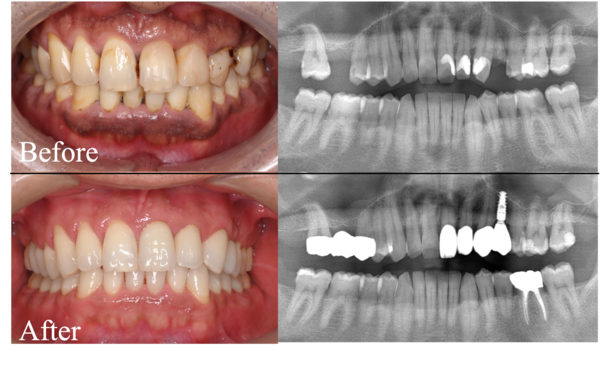

【症例】問題のある部位のみの治療VS全体を見据えた治療計画

自由が丘の歯医者・歯科「三好歯科 自由が丘」は駅徒歩1分、土日診療、ご相談に応じて診療時間外でも対応する通いやすい歯医者です。今回は、口腔内の様々な問題を抱えた患者様の症例です。患者様とご相談の結果、…